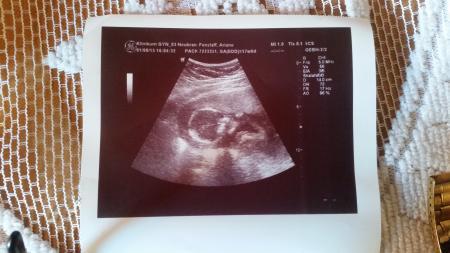

Dann Ultraschall... jaaaa alles i.o. zum glück

Baby hat fleißig Daumen genuckelt

Und gezappelt...

230g wiegt es... aber hat sich nicht gezeigt

Hab noch ne frage gleich... auf mein US sind rechts sone kürzel .. kennt sich da jemand n bissi aus??? Hab schon google gefragt aber der gibt mir keene antworten drauf

Das sind einfach nur Bestimmungen zum Bild. Licht Verhältnisse, Kontrast und solche Sachen. Ich glaube eines davon ist auch schärfe. Ganz harmlos, hat nichts mit dir und dem Baby zu tun.

Ja krümel is schüchtern ^^ Ja mir gehts jetz super Gebährmutter-hals is auch zu und 4cm lang Auch so alles i.o. ....puh zum glück Woche passt auch... ab morgen 19. Ssw... Leider hab i nich erfahren oder nicht mitbekommen wie groß krümel ist.. naja